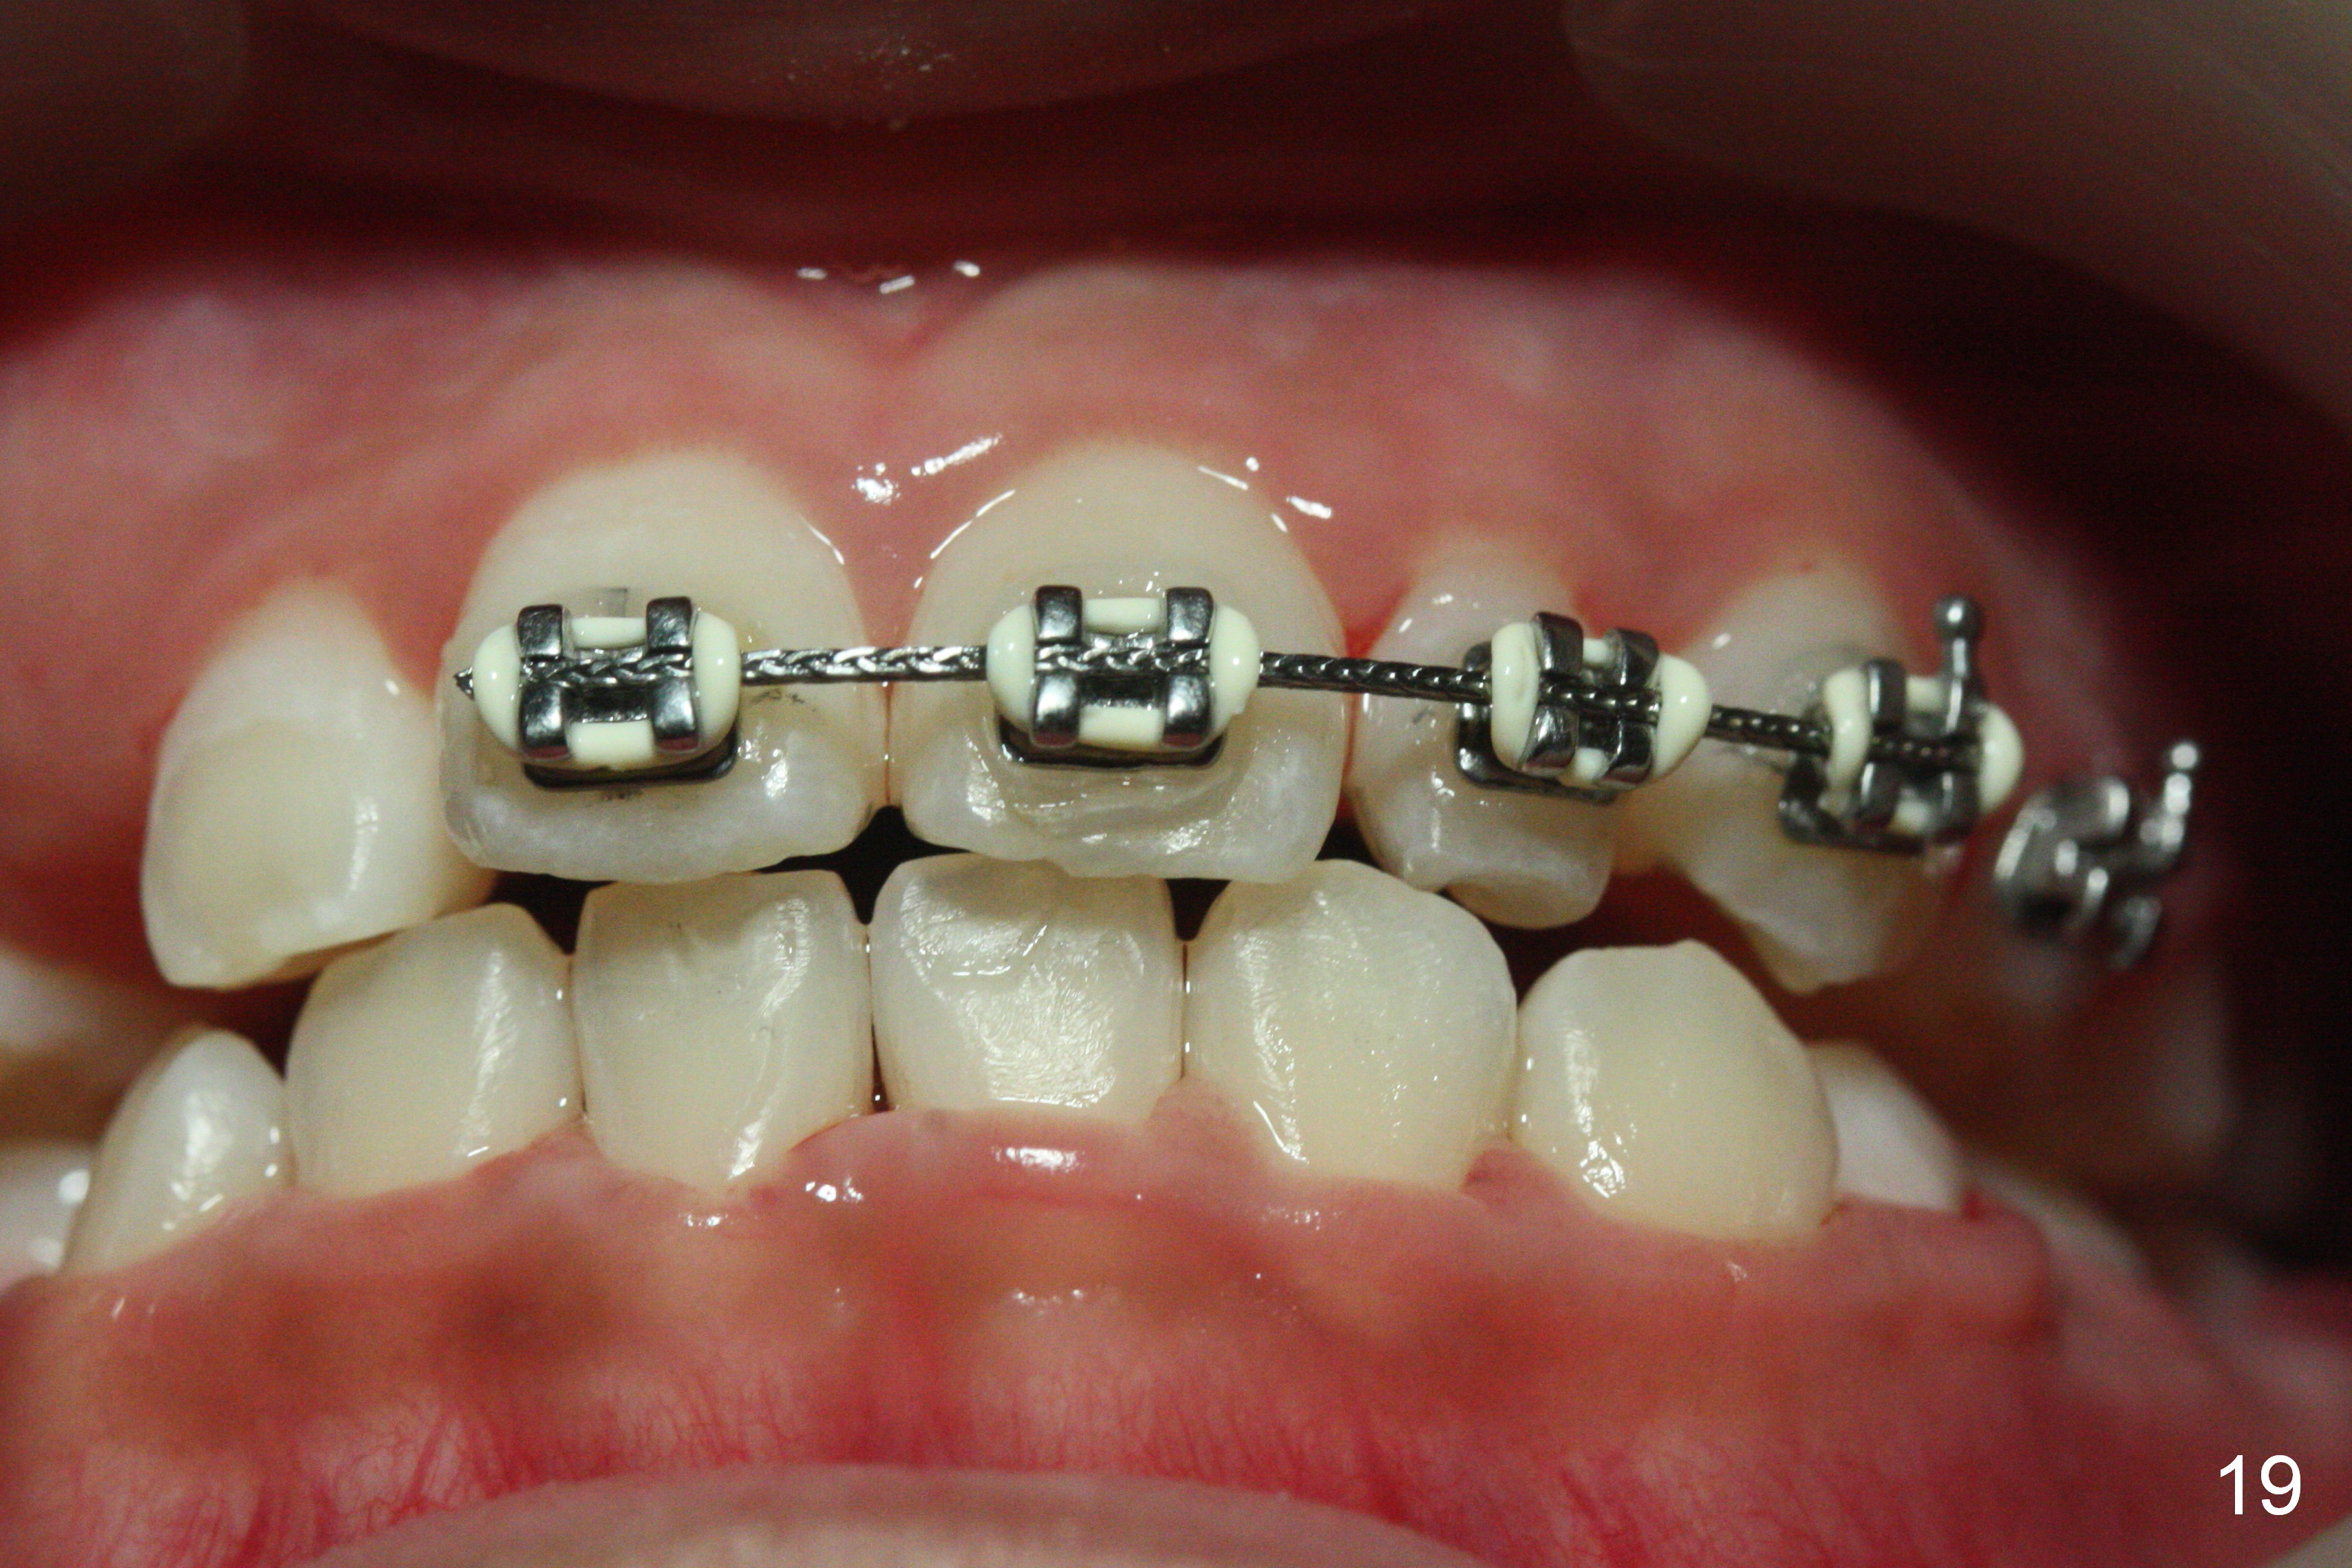

OK Xin, just evaluated the case. If she started with the anterior dental crossbite and you are barely over-corrected right now, I would be very comfortable discontinuing treatment. At her age, there is nothing that can no longer be dealt with beautifully when it is more age appropriate.When anterior cross bite is corrected 19 months post banding, the tooth #10 (microdontia) has tendency of edge-to-edge (Fig.16,17). Power chains are used to create space for #11 to erupt fully before bracketing. In spite of the effort, the peg lateral remains edge-to-edge 23 months post banding (Fig.18,19). The segmental 19x26 braided wire retains as a retainer to prevent #10 from cross bite. The facial profile is more or less normal immediately post debracketing (Fig.20). The anterior occlusion appears to remain basically the same 7 months post debracketing (Fig.21,22). UR3 erupts, while the diastema mesial to UL2 enlarges so that the arch wire appears shorter. UL2,3 appear to be in cross bite 14 months post debracketing, while Es retain at the age of 13 (delayed development, Fig.23).